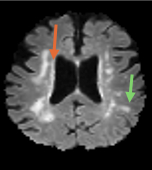

Methods: We included 100 volunteers from GeneSTAR, an ongoing family-based study of families enriched for vascular risk factors and cardiovascular disease, age = 63.3 ± 9.5 years, 60% females, 63% Hypertension, 22% African Americans. Two MRI’s were obtained 10-13 years apart using 3T scanners. At each visit total WMH, PVWMH and DWMH volumes were determined using automated software with consistent co-registration (Figure 1). K2 was measured for each individual by averaging the highest 100 voxels (hotspots) within the regions of interest in each individual lesion using a gadolinium-based DSC-MRI at the second visit (Figure 2). Linear regression models used to analyze the relationship between K2 and volume changes in total WMH, PVWMH, and DWMH, adjusting for age, systolic blood pressure, race, sex, and education.